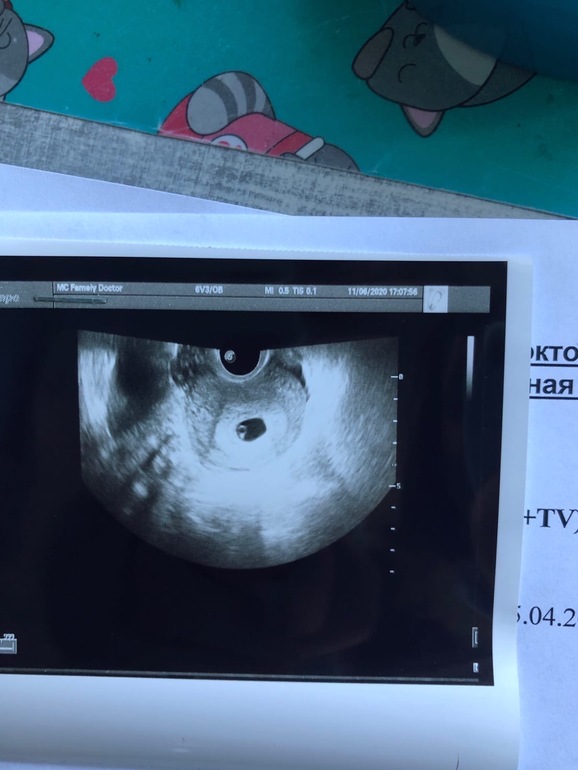

Дядя Рамзи не учёл такого поворота событий 🤷🏻‍♀️🤣 Ну а серьезно, по картинке-узи всёравно где-то есть лево или право😅 просто кто там право, а кто лево, если ПЯ же не плоское, это ж пузырь! Мне на втором узи ели второго эмбриона нашли, он прятался... так что, какой там лево/право... 😂🤭 Да по узи у автора явно ЖМ визуализируется, эмбриона на картинке не видно 🙈

Тут малыш справа 😀тут где то 9 неделя

Вот мой слева это мальчик у меня

У вас по-моему справа прикреплён

вообще-то это лево так что и у вас тогда подтверждается

но говорите что у автора справа как справа если это лево

вообще то это лево